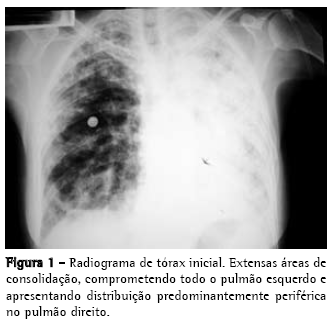

Radiograma e tomografia computadorizada de tórax iniciais, nas Figuras 1 e 2;

Sintomas respiratórios são comuns na SEM e podem estar presentes em até 80% dos pacientes,(14) inclusive como manifestação única. Em uma série de 1.531 casos,(15) tosse ou dispnéia estiveram presentes em 611 deles (59%), e em outro estudo,(16) com 118 pacientes, foram encontrados sintomas respiratórios em 64%, alterações radiológicas em 16% e derrames pleurais em 15%. O acometimento pulmonar confere pior prognóstico e alguns pacientes podem evoluir para insuficiência respiratória aguda.(3,4,17) Os exames complementares, em geral, evidenciam leucocitose e eosinofilia (valores superiores a 3.000/mm3 são mais sugestivos).(11) O radiograma de tórax pode ser normal, apresentar opacidades intersticiais lineares ou reticulonodulares, consolidações pulmonares difusas e derrame pleural.(3,4,10) Os derrames pleurais podem aparecer em até um terço dos casos, e geralmente são exsudatos eosinofílicos.(4,10,16)